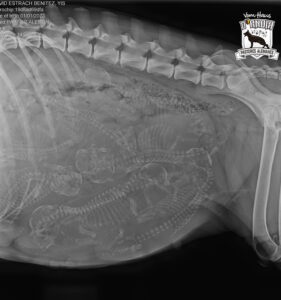

Hoy martes 14 de Abril le hemos hecho a Yis de Usurbe la radiografia de fin de embarazo. La perra lleva 9 cachorros, así que …